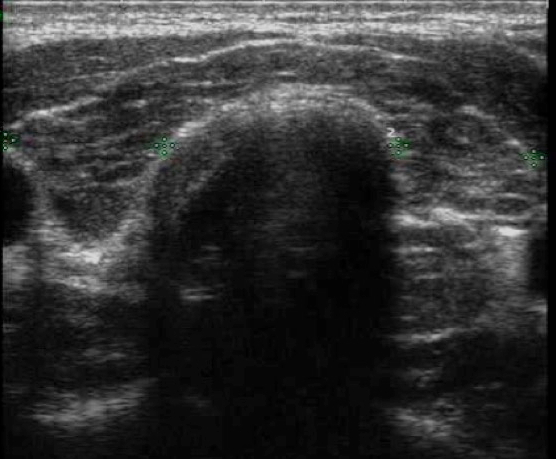

Il linfoma della tiroide, primitivo o espressione di una malattia sistemica, si presenta generalmente come un gozzo teso e dolorabile, spesso con caratteristiche ecografiche simili alla tiroidite di Hashimoto. Il pattern ecografico tipico del linfoma tiroideo è costituito da una massa solida nell’ambito di una ghiandola fortemente aumentata di volume, ipoecogena (rispetto al tessuto tiroideo circostante) o, più spesso, molto ipoecogena (rispetto ai muscoli pre-tiroidei), con caratteristiche variabili dei margini (7,8) (fig. 4). L’ipoecogenicità è in questo caso dovuta sia all’aumento delle cellule infiammatorie che neoplastiche.

Figura 4. Linfoma tiroideo